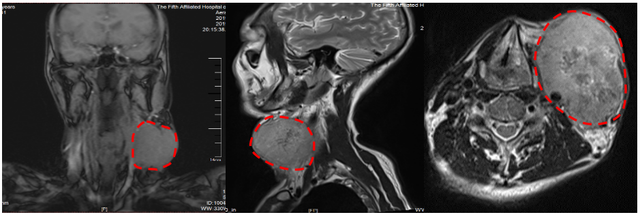

成人拳頭大小的淋巴結(jié),到底因何而起?醫(yī)生說,這病好發(fā)于50-60歲男性。中山大學(xué)附屬第五醫(yī)院腫瘤中心劉志剛副主任說:“該患者第一次就診的情形,我印象深刻,他的頸部淋巴結(jié)約1084cm,有成人拳頭大小,活動(dòng)十分困難?!?019-8頭頸部核磁共振1年前,王某左頸部長(zhǎng)了個(gè)巨大淋巴結(jié),被確診為喉癌,曾在外地就診,但病情嚴(yán)重,治療效果不佳。2020-6頭頸部核磁共振一年后腫瘤幾乎消失,他做了哪些治療?經(jīng)過根治性放射治療和同步化療、靶向治療近一年后,目前,該患者的腫瘤幾乎完全消失,左頸部腫大淋巴結(jié)基本消退,生活質(zhì)量明顯改善。該患者還特地帶來了蛋糕與醫(yī)護(hù)人員一起慶祝他的60歲生日。據(jù)悉,喉癌是比較常見的惡性腫瘤,病因尚不十分清楚,但絕大多數(shù)患者有長(zhǎng)期抽煙史,好發(fā)于50-60歲男性。劉志剛主任提醒市民,不要過度飲酒;平時(shí)保持良好的口腔衛(wèi)生習(xí)慣;少吸煙或戒煙;如患慢性炎癥要及早治療。出現(xiàn)以下癥狀,要及時(shí)到正規(guī)醫(yī)院??凭驮\1.頑固性聲音嘶?。翰幻髟虻穆曇羲粏∈窃缙谧畹湫偷陌Y狀,一般持續(xù)兩周以上且對(duì)癥治療無效。如腫瘤向下侵犯,可出現(xiàn)聲音嘶啞,腫瘤增大阻塞喉腔可引起呼吸困難;2.咽喉感覺異常:異物感、緊迫感、吞咽不適是聲門上型喉癌的早期癥狀;3.痰中帶血:由腫瘤刺激引發(fā)的刺激性干咳,往往痰中帶血并呼吸困難;4.反射性疼痛:喉癌合并潰瘍、炎癥、喉軟骨骨膜炎或發(fā)生潰爛后,可有咽喉疼痛或干咳,或引起神經(jīng)的反射性疼痛,表現(xiàn)為同側(cè)頭痛、耳痛;5.淋巴結(jié)腫大:聲門上區(qū)淋巴組織豐富,可較早出現(xiàn)頸淋巴結(jié)腫大。聲門上型喉癌生長(zhǎng)極快,易發(fā)生早期頸淋巴結(jié)轉(zhuǎn)移,一旦出現(xiàn)癥狀,大多已經(jīng)是晚期。